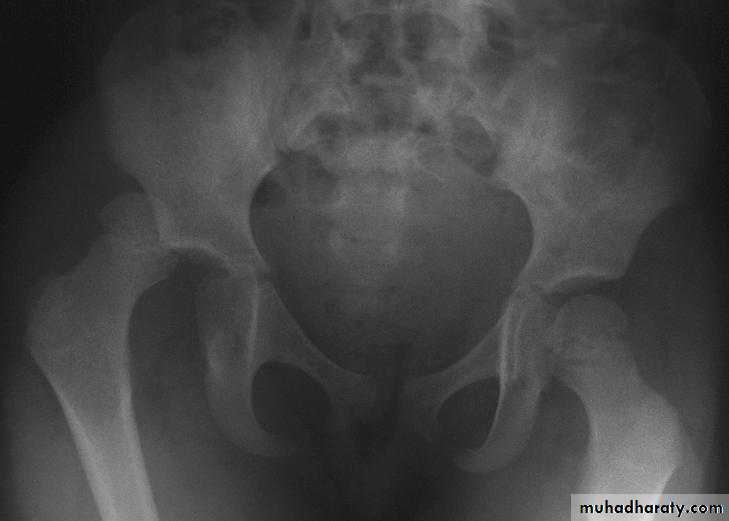

Inter-trochanteric fractures (extracapsular fracture)

.It is extra capsular fracture occurs in elderly.

.Unite quite easily and seldom cause a vascular necrosis.

Pathological anatomy divided into:

Stable:

Unstable are those where

a. posteriomedial cortex is shattered.

b. poor contact between fracture segment.

Radiological examination

2 types

Stable.

Unstable.